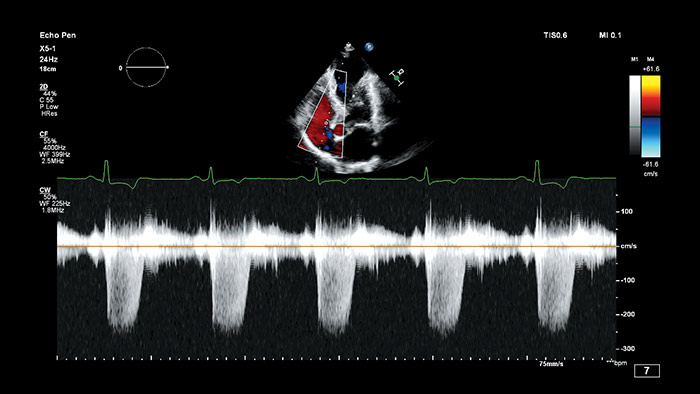

Anatomical Intelligence for Ultrasound (AIUS) di Philips, una tecnologia progettata per potenziare il sistema ecografico. Funzionalità avanzate di modellazione degli organi, sezionamento delle immagini e quantificazione convalidata per agevolare l'esecuzione degli esami e favorirne la riproducibilità, che offrono nel contempo nuovi livelli di informazioni cliniche per rispondere alle sfide economiche e cliniche poste dagli ambienti sanitari odierni.

Le funzionalità AIUS spaziano dall'automazione di passaggi ripetitivi fino all'analisi computerizzata completa di dati non elaborati, con una minima interazione da parte dell'operatore. AIUS è in grado di fornire una documentazione di screening avanzata e misurazioni assistite, oltre al rilevamento di organi e strutture per la registrazione automatica e la quantificazione avanzata.